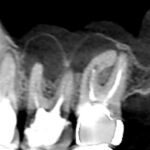

精密根管治療を行い、根の先までしっかり根管充填をすることを心がけました。画像は根管充填時のレントゲン写真です。根の先まで根管充填材が届いています。

精密根管治療6ヶ月後の経過観察時のCT画像です。青い矢印の先にあった膿の影が消失し歯槽骨が再生しています。